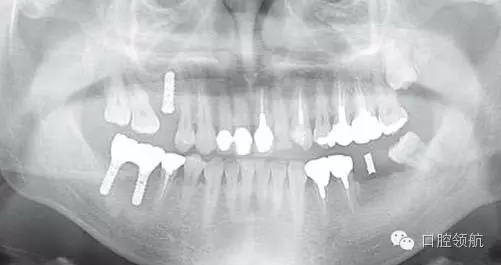

對患者進行詳細說明后,拔除后等待骨愈合6個月,再度植入手術(shù)。第二次植入時,注意了沖水充分,根據(jù)骨的狀態(tài),在缺損部中央植入。植入后2個月,按常規(guī)戴入上部結(jié)構(gòu),約6個月后,曲面斷層影像和口內(nèi)均未見異常,愈合良好(圖9)。

圖9 再植入后6個月的曲面斷層影像。